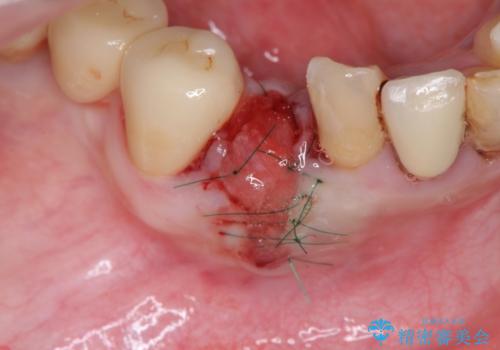

X線写真および歯周組織検査より、歯の破折 周囲骨の高度な吸収が認められました。

抜歯後、インプラントによる審美・機能改善を希望されたのでインプラント埋入に先立ち吸収した骨の再生を計画します。

歯を失う原因が虫歯や根尖病変などはなく、歯周病や歯の破折等周囲の骨を吸収する原因の場合はインプラント治療を行うに先立ち骨の造成が必要なことがあります。